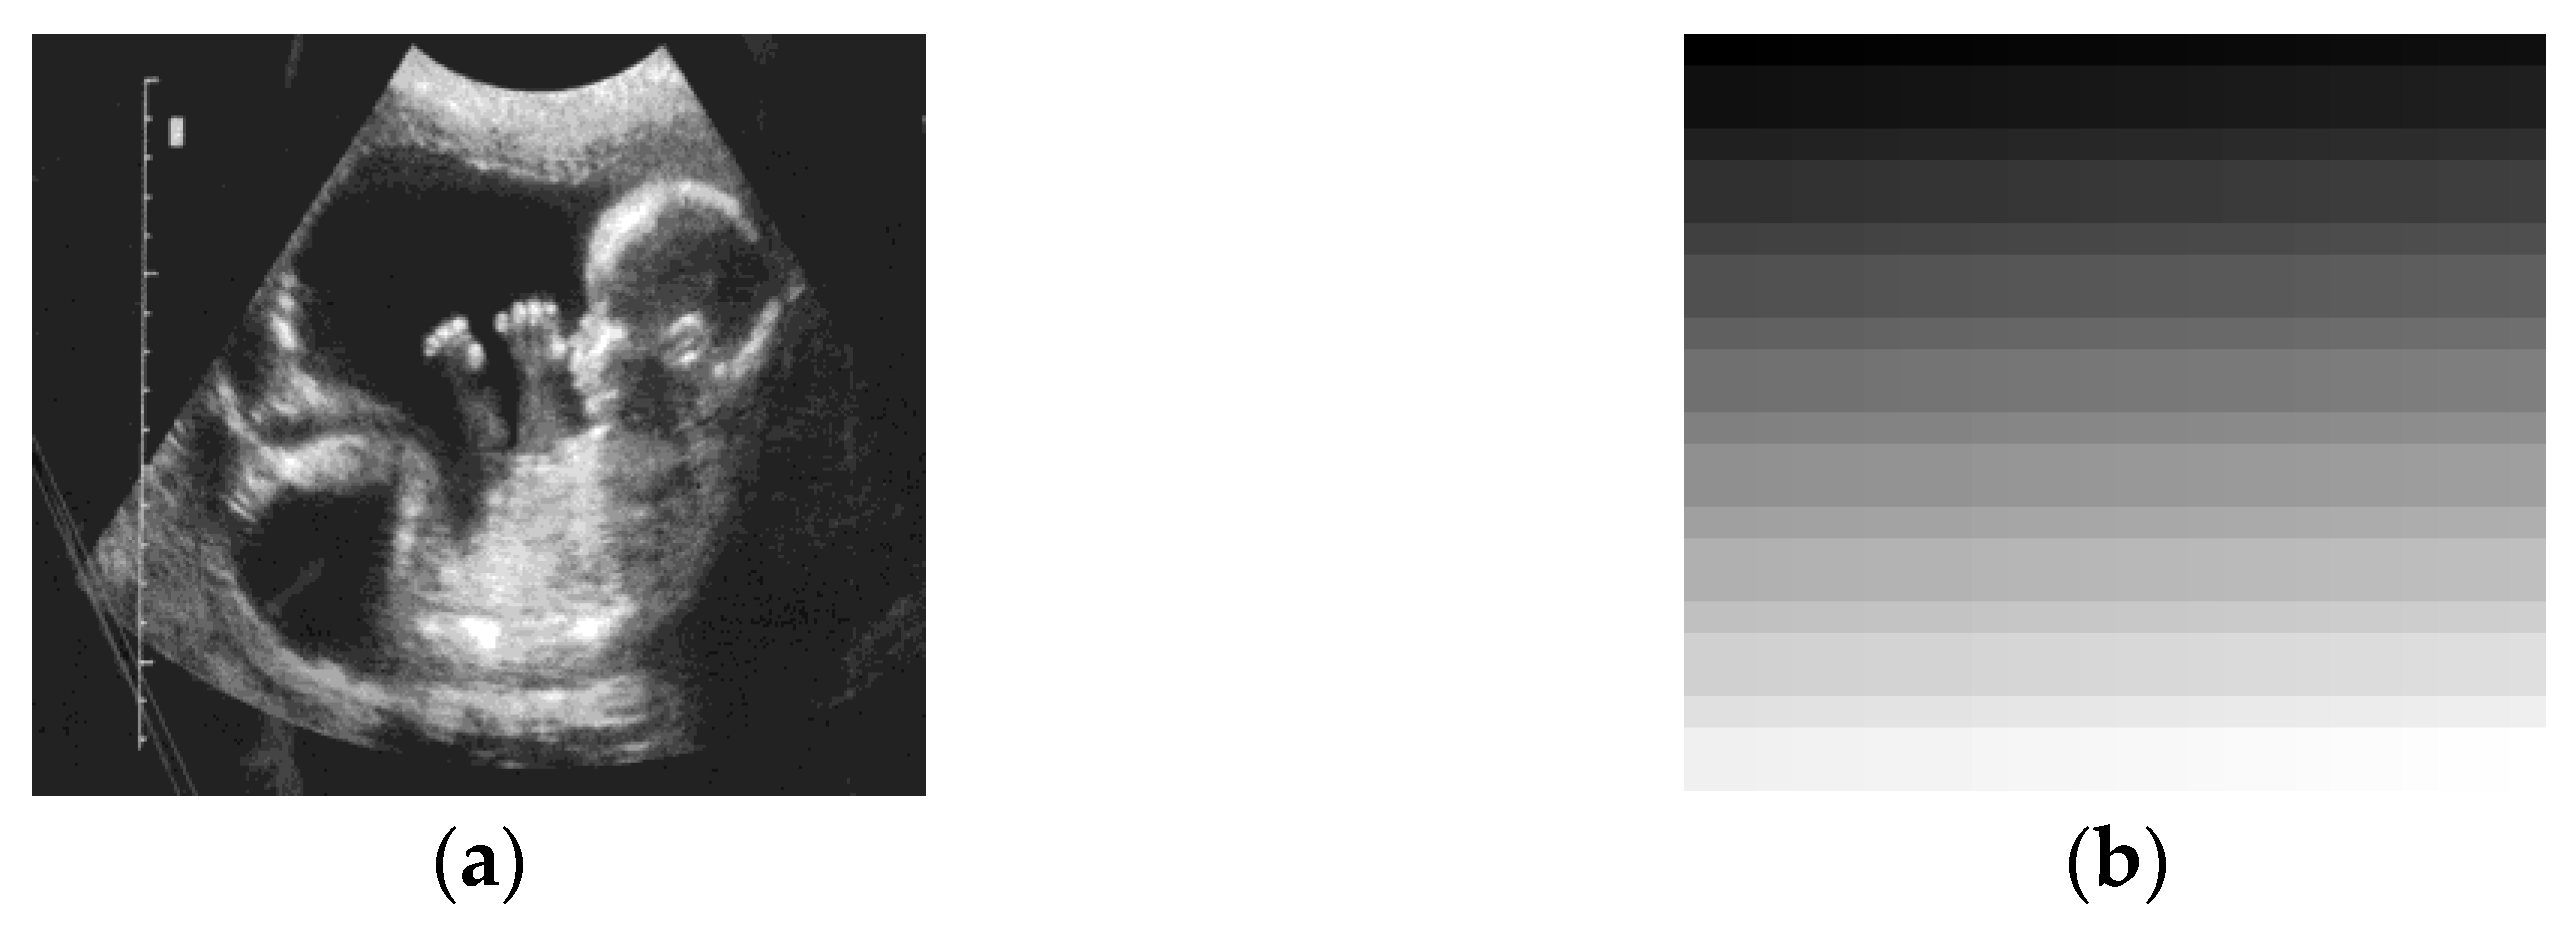

| PEI | ![]() | ![]() | ![]() | ![]() | ![]() | ![]() | ![]() |